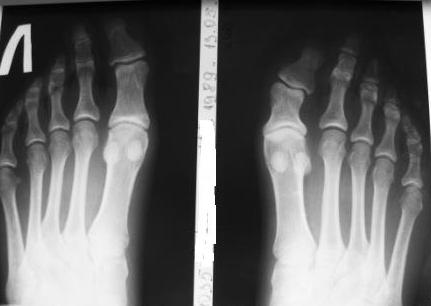

Re: Дисплазия фаланги пальца стопы

Рентгенограммы прилагаю.